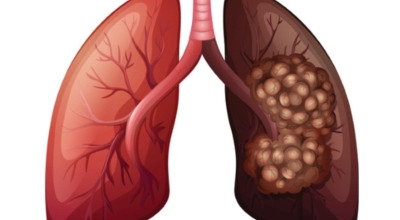

폐암이란?

폐암은 폐에 생기는 악성 종양을 말합니다. 폐에서 직접 발생하는 원발성 폐암과, 다른 장기에서 전이되어 온 전이성 폐암으로 나눌 수 있어요. 전 세계적으로 매년 약 130만 명이 폐암으로 사망하는데, 이는 암으로 인한 사망 원인 중 가장 높은 비중을 차지하고 있습니다.

폐암 초기 증상 중 하나로 가슴 통증이 있습니다. 폐암 환자의 약 3분의 1 정도가 흉통을 호소하는데요, 이는 폐 가장자리 부분에 종양이 생기고, 그 종양이 암세포를 생성하며 흉벽과 흉막에 닿아 통증을 유발하기 때문입니다.

흉통은 여러 원인으로 발생할 수 있지만, 폐암에서 기인한 흉통은 지속적으로 쿡쿡 찌르는 듯한 느낌과 함께 가벼운 통증이 아닌 둔탁한 통증이 동반되는 경우가 많으니 주의가 필요합니다.